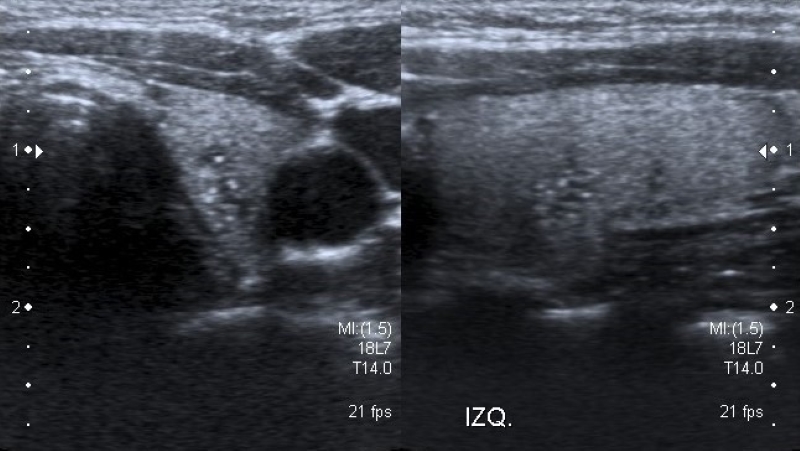

Describe el componente interno del nódulo, identificando la presencia de contenido sólido (Fig. 1) o quístico (Fig. 2), y en los casos de nódulos mixtos (Fig. 3) la proporción de cada uno (predominantemente sólido/ predominantemente quístico). Cuando se evalúa un nódulo parcialmente quístico es importante caracterizar su componente sólido indicando además si tiene localización central o periférica (esta última podría asociarse con mayor riesgo de malignidad)13.

Los nódulos completamente quísticos son considerados benignos2,14,15) y los sólidos se asocian mayormente a malignidad15,16, pero hay descriptos nódulos sólidos benignos, como así también nódulos confirmados como CPT con componente mixto2,15,17.

Existen otro tipo de nódulos, los espongiformes, que presentan un patrón mixto con múltiples quistes pequeños en su interior, y tienen un muy bajo riesgo de Malignidad2,13,14,18.